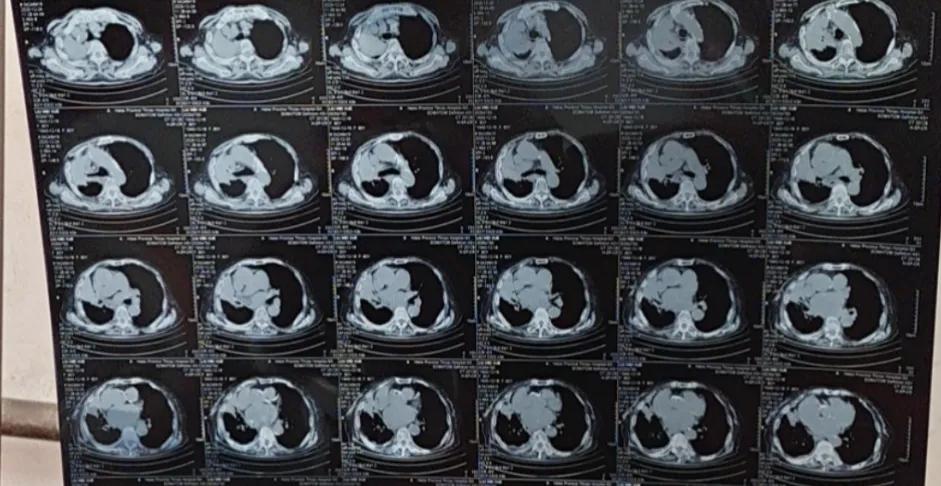

Our criteria for judging tumor improvement are not based on symptoms but on examination results, especially imaging findings. For lung cancer, CT scan results are primarily used. If the CT scan shows tumor shrinkage, we consider the disease to be improving. If the results show tumor growth, regardless of whether the symptoms have improved, we consider the disease to be progressing.

After Mr. Liu's son returned, he managed to bring his father to the hospital for chemotherapy through persuasion and some coaxing. After two cycles of chemotherapy, a follow-up CT scan showed that the tumor had significantly shrunk, the tumor was under control, and his physical condition had not deteriorated.